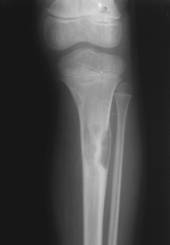

a)   Fibromul – apare ca o zona transparenta metafizara, excentrica, ovalara, conturul intern fiind marginit de o zona sclerozata. Corticala este subtiata, uneori disparuta. Rareori se poate observa o slaba reactie periostala. Afecteaza cu predilectie varsta adulta.

Fig. 83 – Fibrom tibial